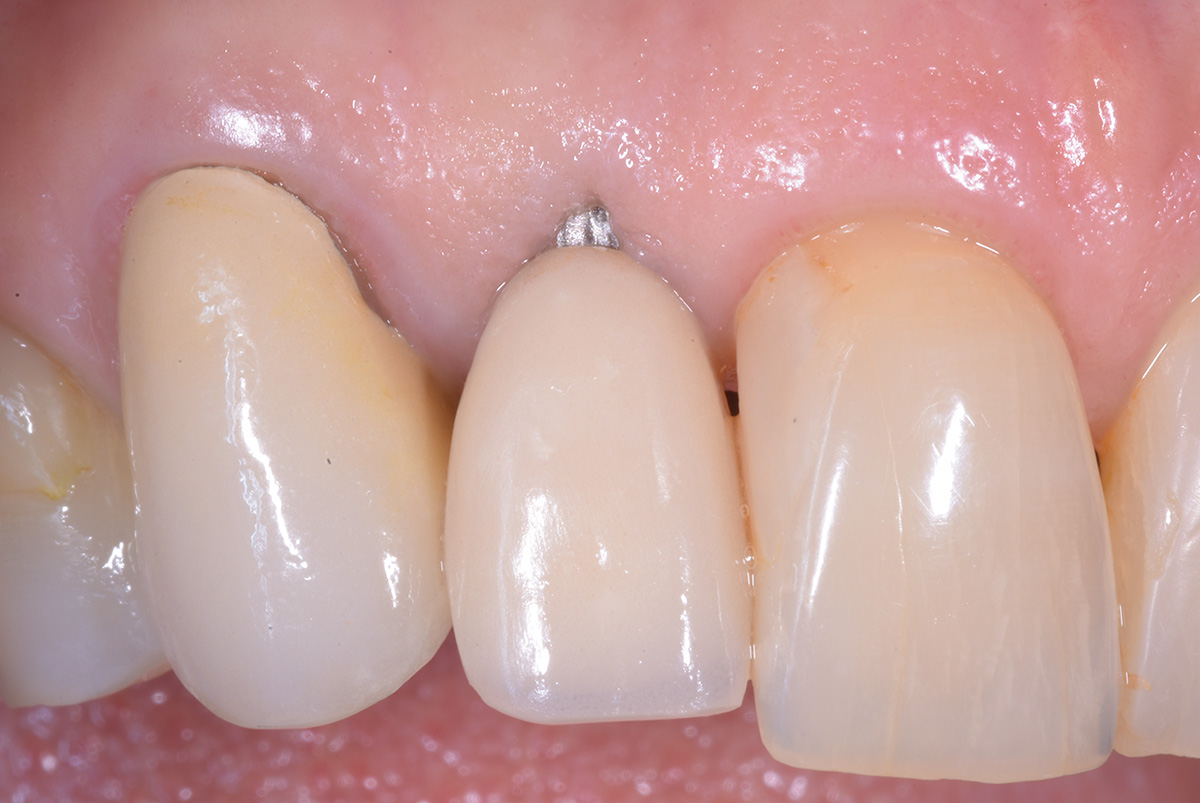

Correzione estetica mucogengivale, mediante innesto di connettivo, di esposizione impianto di incisivo laterale sup dx, con rifacimento protesico di laterale e canino.